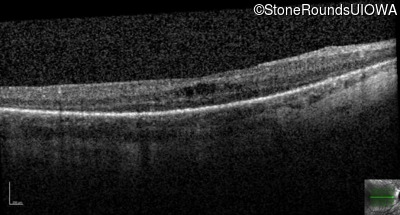

Optical Coherence Tomography - Right - 20/40

Exemplar / OCT Stack